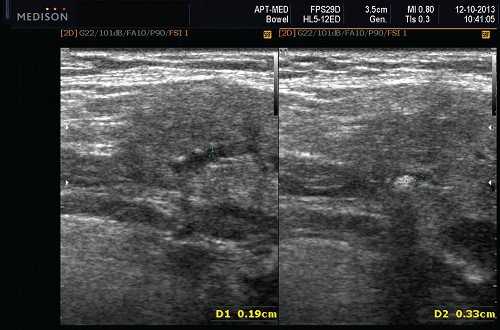

Морфология. Малая плеоморфная аденома: одиночная, цельная, яйцевидная и хорошо разграниченная опухоль. Большая плеоморфная аденома на УЗИ: дольки ± кровоизлияние или некроз ± кальцификация

Серошкальное УЗИ. Хорошо выраженная, солидная и гипоэхогенная по сравнению с прилегающей тканью слюны. Однородная внутренняя эхо-структура с задним акустическим усилением. Опухоль имеет несколько тканевых границ и позволяет звуку легко проникать, вызывая улучшение заднего отдела. Большие опухоли могут иметь неоднородные внутренние эхосигналы из-за кровоизлияния и некроза. Гетерогенная плеоморфная аденома может иметь нечеткие границы, имитирующие злокачественную опухоль. Большие опухоли могут иметь дольки и появляться на ножке. Необычный кальциноз при ультразвуковом сканировании наблюдается при давней опухоли. Кожа и подкожные ткани в норме